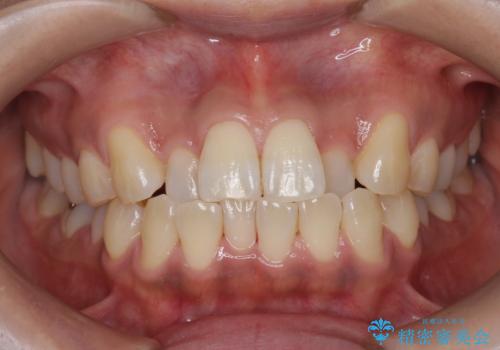

数年ぶりの歯医者で歯を白くしたい